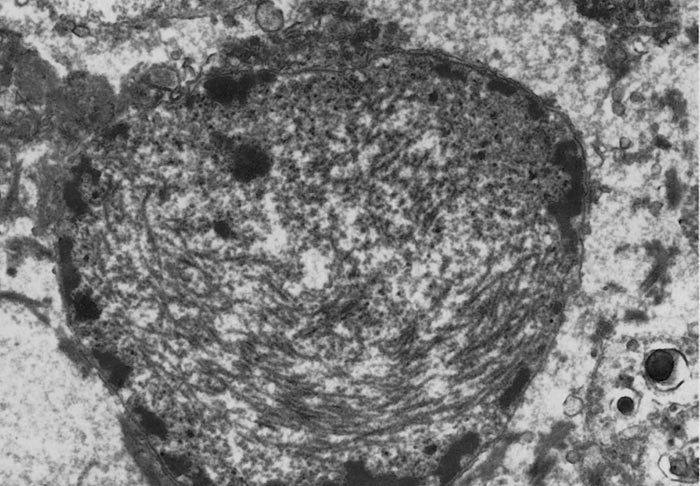

Rift Valley fever virus is a member of Phlebovirus genus, family Phenuiviridae of the order Bunyavirales.374 The viral particles are spherical, 80 to 120 nm in diameter (Figure 1), and consists of an envelope and a ribonucleocapsid (RNP). The envelope is composed of a host cell-derived lipid bilayer containing heterodimers of virus encoded glycoproteins, which are the building blocks of 122 capsomers118 (110 hexamers and 12 pentamers) arranged in T – 12 lattice.554 It has a three-segmented, single-stranded, negative-sense RNA genome of about 12 kb comprised of large (L, 6.4kb), medium (M, 3.8kb) and small (S, 1.6kb) segments. The L and M segments are of negative polarity. The L segment encodes the RNA-dependent RNA polymerase (L protein). The M segment encodes four proteins in a single open reading frame: the precursor to the structural glycoproteins Gn and Gc and two non-structural proteins designated NSm1 and NSm2. The S segment utilizes an ambisense orientation to encode two proteins, the nucleocapsid protein (N) and a non-structural protein (NSs).76, 238, 506 The NSs forms a ribbon-like filament in the nucleus 578, which is particular to RVFV and not shared with the NSs proteins of other bunyaviruses. Rift Valley fever virus replication cycle is similar to that of other negative-stranded RNA viruses76 and involves three major processes: 1. attachment, uptake and fusion, 2.primary transcription, transcription and replication, and 3.virus assembly and release.